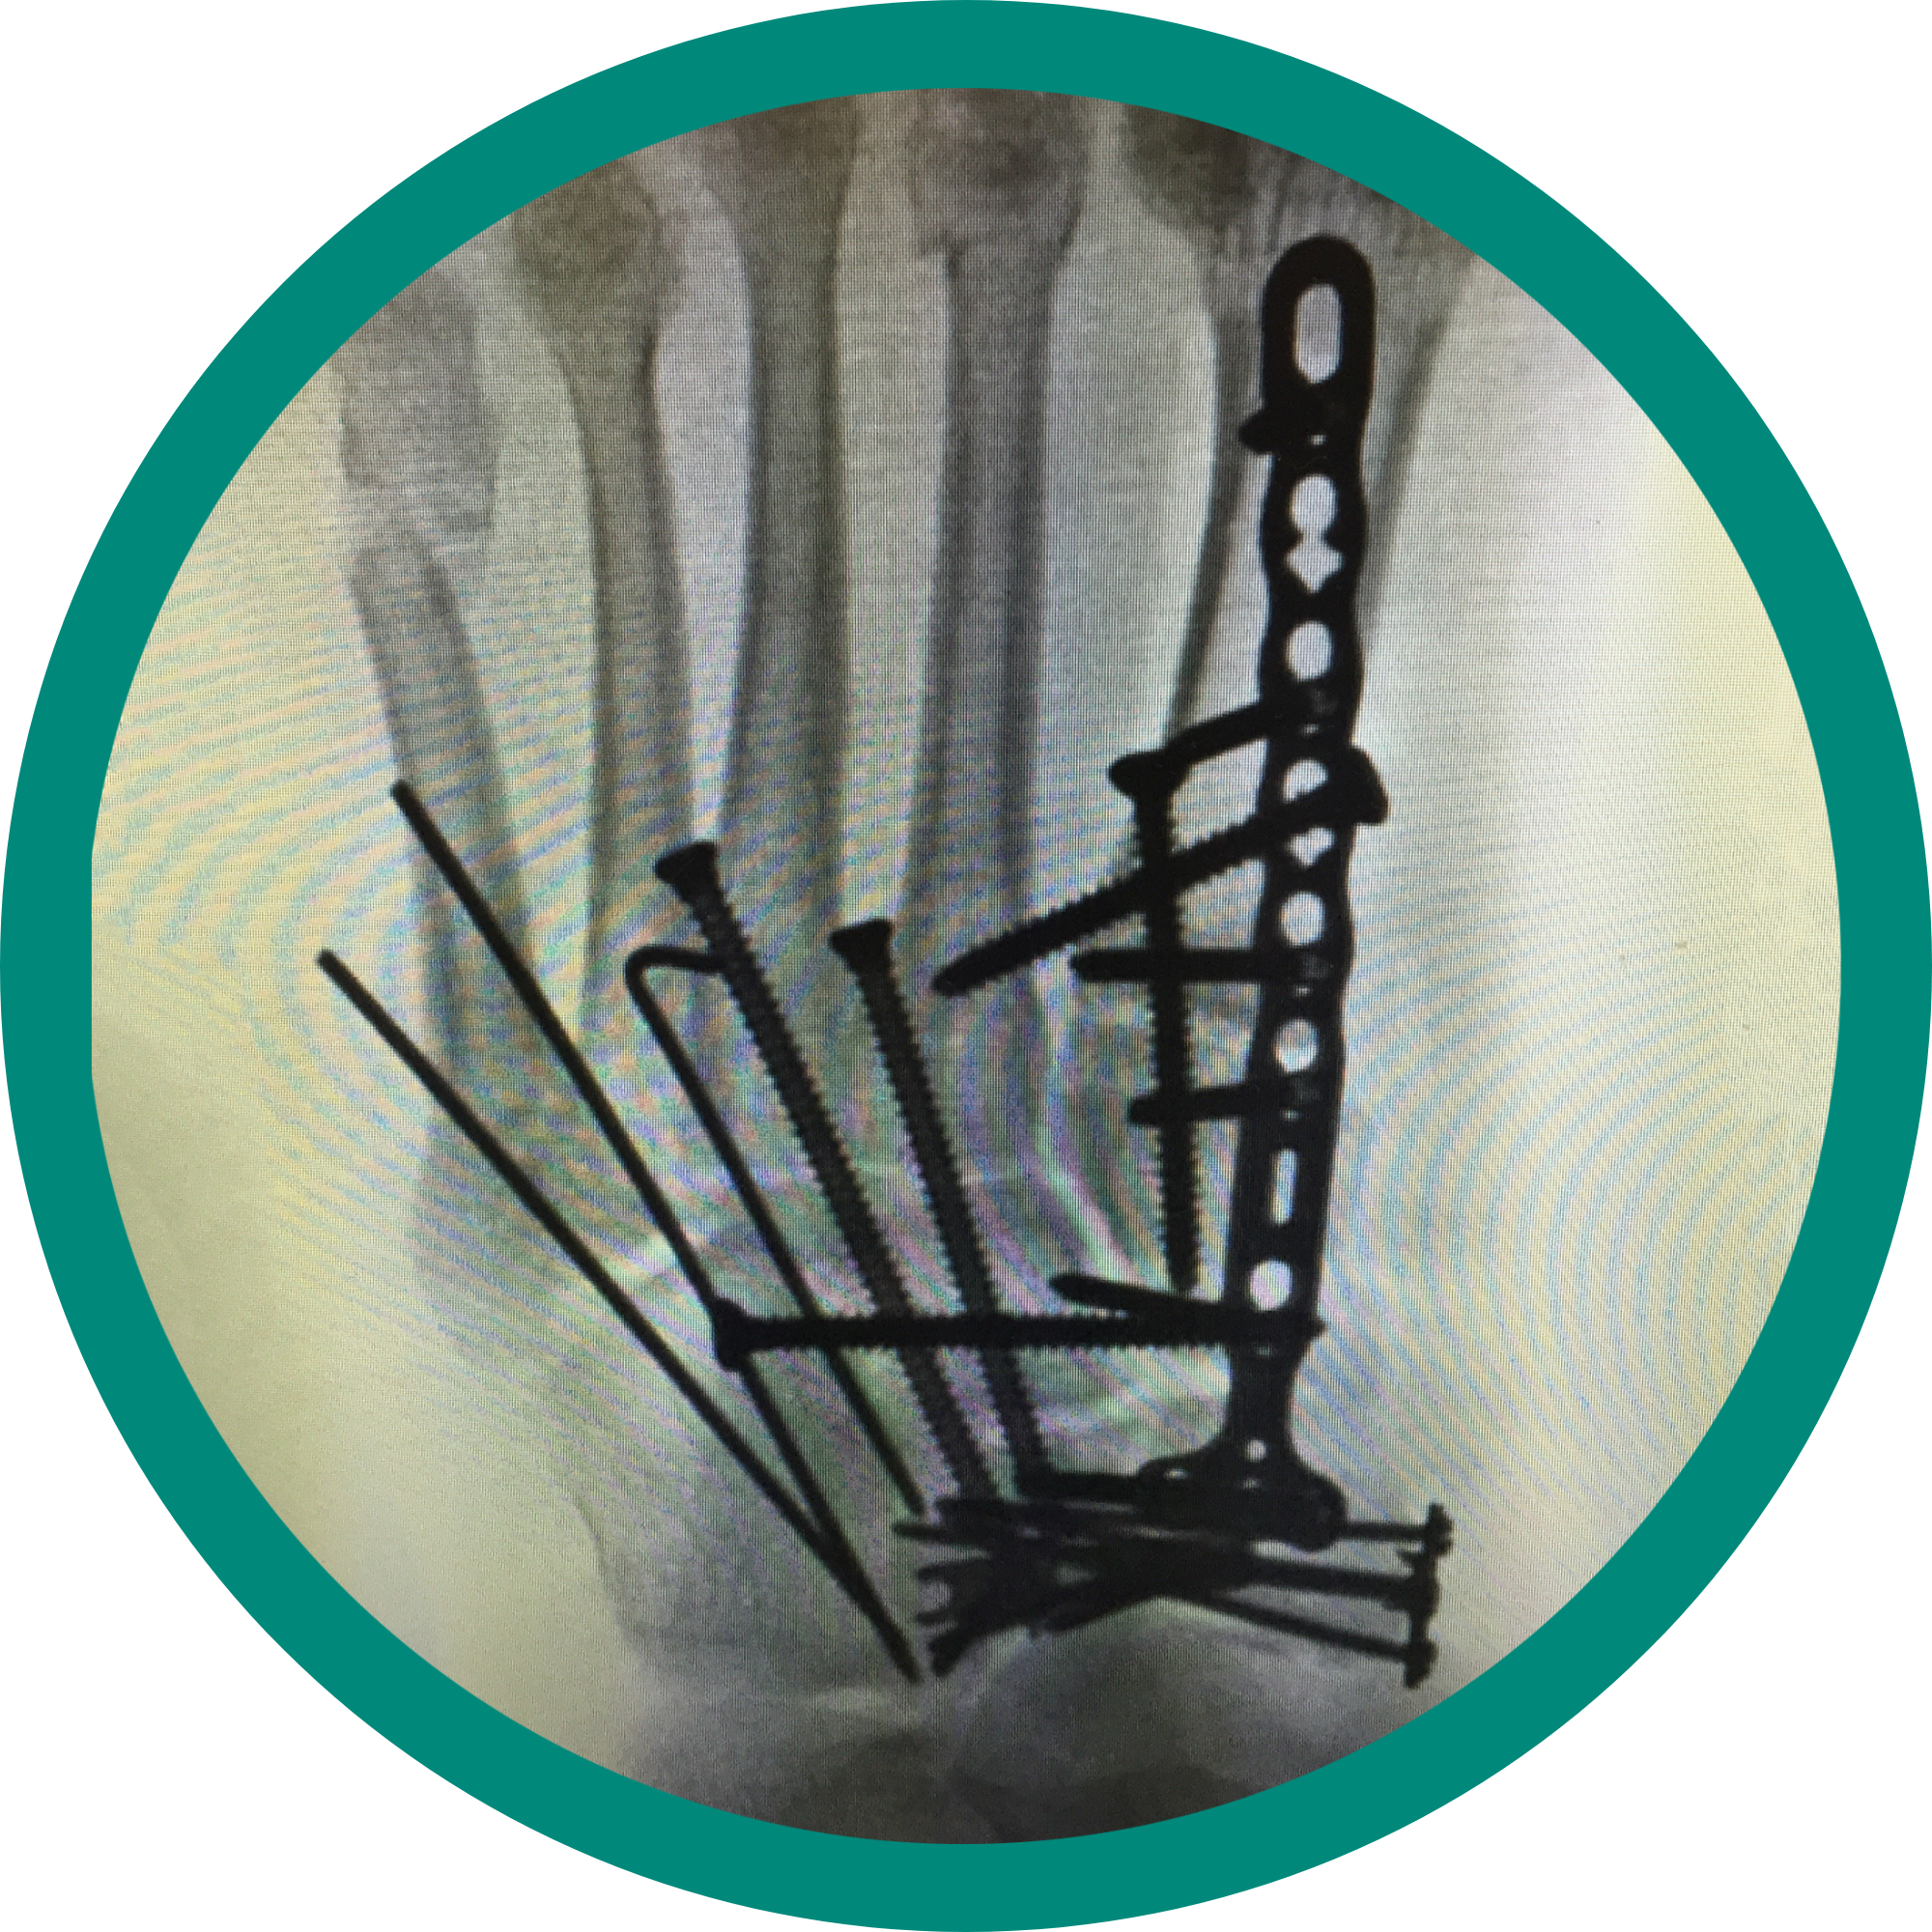

Complex trauma

Dr. Stevens’ practice is one of the few foot and ankle specialists in Illinois. He provides various care options including, but not limited to, revision surgeries, reconstruction fusions and complex trauma repairs. He also ranks in the Top 1% in patient experience nationally.

Complex reconstruction